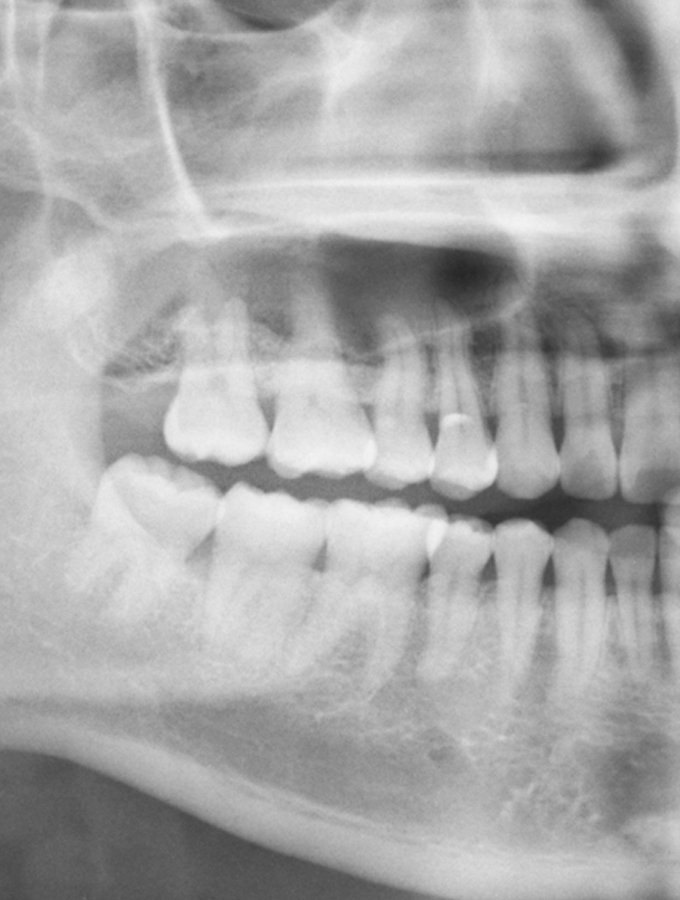

Οι φρονιμίτες ( ή αλλιώς σωφρονιστήρες ) είναι τα τελευταία δόντια τα οποία ανατέλλουν στη στοματική κοιλότητα, κατά την ηλικία των 17-23, αν και μπορούν να συνεχίσουν να ανατέλλουν μέχρι και την ηλικία των 30 ετών. Συνήθως είναι δόντια με αρκετά ιδιόμορφη μορφολογία. Κατά την ανατολή τους, μπορεί να έρθουν σε επαφή με τον 2ο γομφίο, ο οποίος βρίσκεται ακριβώς από μπροστά, ή να μην έχουν τον απαιτούμενο χώρο ώστε να προβάλλουν στο στόμα και να διαταχθούν ομαλά σε σχέση με τα πιο πρόσθια δόντια. Και οι δύο καταστάσεις έχουν σαν αποτέλεσμα την έγκλειση του δοντιού στη γνάθο η οποία μπορεί να είναι ασυμπτωματική ή και συμπτωματική. Η εντονότερη συμπτωματολογία αφορά συνήθως τους φρονιμίτες της κάτω γνάθου και σπανιότερα της επάνω λόγω των πιο περίπλοκων ανατομικών συνθηκών που υπάρχουν στην οπίσθια περιοχή της κάτω γνάθου.

Ένας φρονιμίτης που είναι πλήρως καλυμμένος από οστό ή ούλα ονομάζεται έγκλειστος ενώ αυτός που έχει μερικώς «τρυπήσει» τα ούλα λέγεται ημιέγκλειστος. Ο ημιέγκλειστος φρονιμίτης είναι συνήθως περισσότερο συμπτωματικός λόγω της κατακράτησης τροφών στην περιοχή μεταξύ του δοντιού και των ούλων, καθώς και της αδυναμίας καλού καθαρισμού τηε περιοχής με την καθημερινή στοματική υγιεινή ( βούρτσισμα-διάλυμα ). Η είσοδος των τροφών έχει σαν επακόλουθο την κατακράτηση μικροβίων και συνεπώς τη μόλυνση και φλεγμονή της περιοχής, που ονομάζεται περιστεφανίτιδα.

Οι έγκλειστοι φρονιμίτες παρουσιάζουν σπάνια περιστεφανίτιδα . Πολύ συχνότερα όμως, προκαλούν καταστροφή του οστού που στηρίζει τον 2ο γομφίο ( λόγω κλίσης του φρονιμίτη και έντονης επαφής των δύο δοντιών ), μ’ αποτέλεσμα τη δημιουργία περιοδοντικού προβλήματος, καθώς και στρεβλοφυία των μπροστινών δοντιών, από την έλλειψη χώρου και την πίεση που προκαλεί.